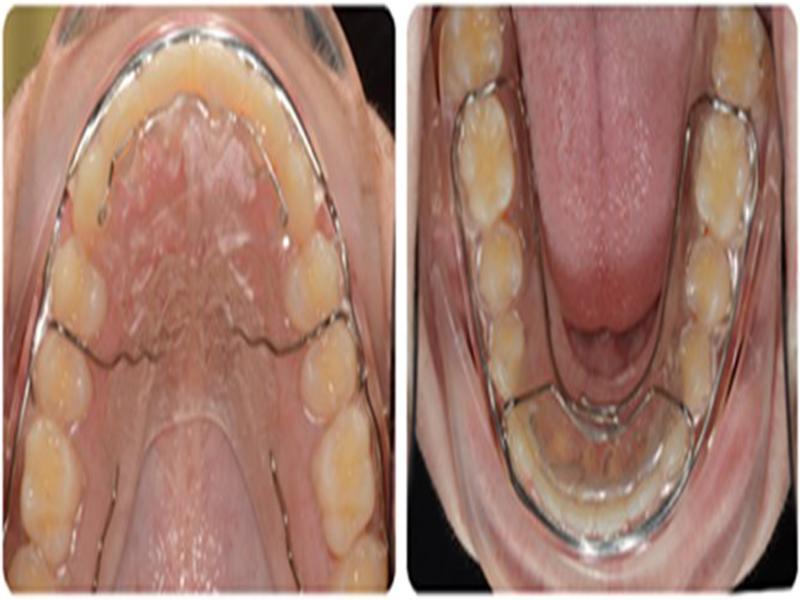

Figure 3.